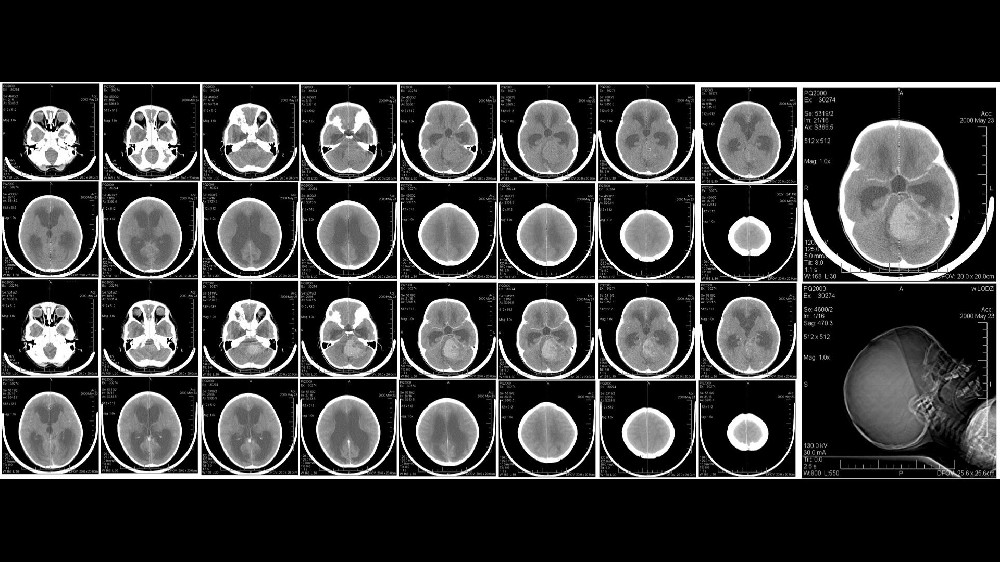

髓母細胞瘤的病程分為四個不同的臨床階段,分別顯示腫瘤的位置、大小和轉移擴散情況。了解這些階段和相關的存活率,特別是與香港和亞洲人口相關的階段和存活率,有助於調整病人的期望,鼓勵及早介入治療。

第 1 期 - 早期髓母細胞瘤

第一期的髓母細胞瘤通常較小、定位精確,且擴散程度極低。在此早期階段發現的腫瘤可提供更多的治療機會,預後也非常良好。

通常僅限於直徑小於 3 公分的單一可切除腫塊。

標準治療包括手術切除,通常會結合局部放射治療。

包括香港和亞洲醫院的數據在內的經驗證據顯示,85% 在治療後 5 年的存活率令人鼓舞。

第 2 期 - 中期髓母細胞瘤

在第 2 期,髓母細胞瘤在空間上仍相對有限,但可能有輕微的組織侵犯或體積增大,對於完全切除手術提出了更高的挑戰。

腫瘤超過 3 公分,或腫瘤侵犯附近的小腦結構。

治療方案通常包括綜合手術、專門針對殘留癌細胞而設計的大範圍放射治療,偶爾還會進行化療。

亞洲患者群組的五年存活率仍然很高,根據香港腫瘤中心的臨床試驗統計,存活率介於 70%-85% 之間 (2024)。

第 3 期 - 晚期髓母細胞瘤

第 3 期髓母細胞瘤的特徵是腫瘤的侵襲性和局部擴散性增加,尤其是沿著腦脊液路徑擴散,對治療造成相當大的挑戰。

區域性擴散至整個腦脊液路徑,通常會達到腦部或脊髓的其他部分。

密集的多模式治療通常會結合手術、覆蓋較大中樞神經系統區域的放射線治療,以及定期的侵略性化療週期。

亞洲腫瘤學界的實際治療資料,特別是香港醫療機構的出版物顯示,由於治療複雜,5 年存活率在 50-70% 之間。

第 4 期 - 轉移性或高風險髓母細胞瘤

第 4 期是由中樞神經系統內或以外的遠端轉移所決定,代表一種侵略性、具挑戰性的臨床情況。

廣泛的轉移發病可達到遙遠的中樞神經系統地區,有時甚至是顱外,使得治療策略變得非常複雜。

複雜的系統療法整合了廣泛的化療、基於新陳代謝腫瘤學原理的尖端標靶治療(包括葡萄糖新陳代謝抑制或谷氨酰胺新陳代謝靶向),以及全面的放射策略。

亞太地區臨床研究報告的存活率顯示,髓母細胞瘤在診斷後三年的存活率只有 20-35%,但研究進展顯示,透過新穎的治療策略,例如由劉國龍教授等專家開創的代謝療法,以及 2024 年發表在《自然醫學》上的研究,髓母細胞瘤有可能變成一種可控制的慢性疾病。